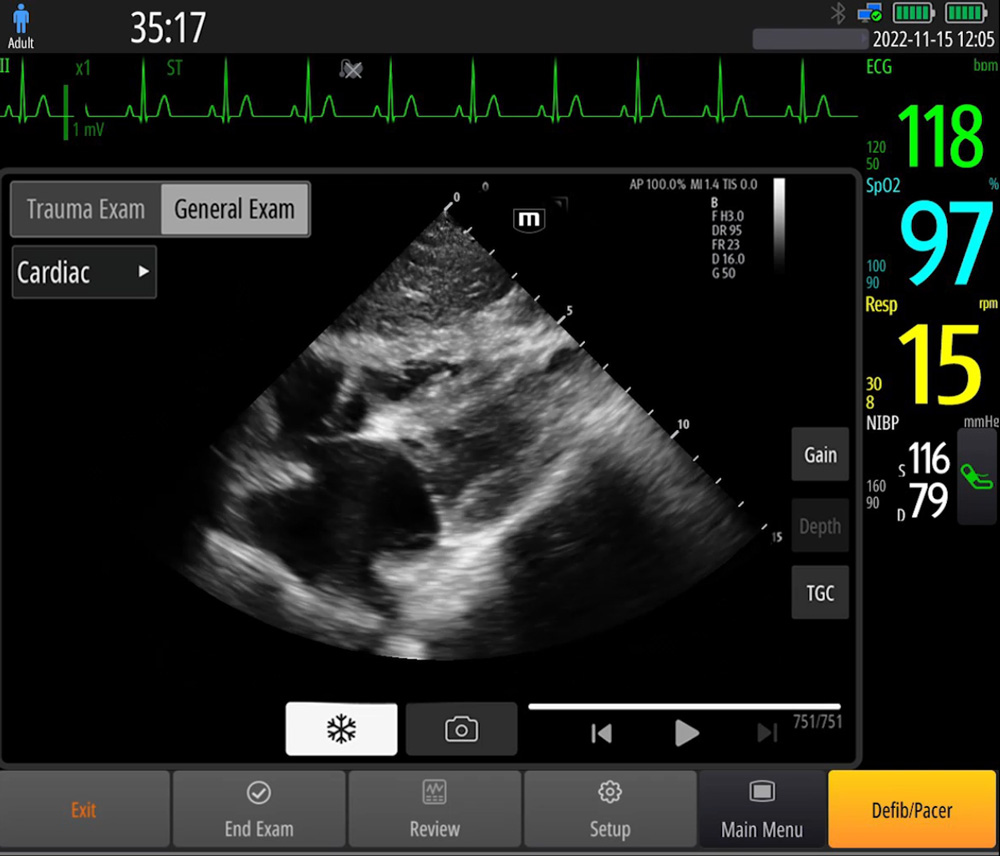

Point-of-Care-Ultraschall (POCUS)

Die integrierten Ultraschallfunktionen verbessern die Diagnose vor Ort erheblich. Dank der intelligenten Bedienungsanleitung k?nnen effiziente Ma?nahmen einfacher ergriffen werden.

- Phased-Array-Sonde: hohe Aufl?sung, weit verbreitet